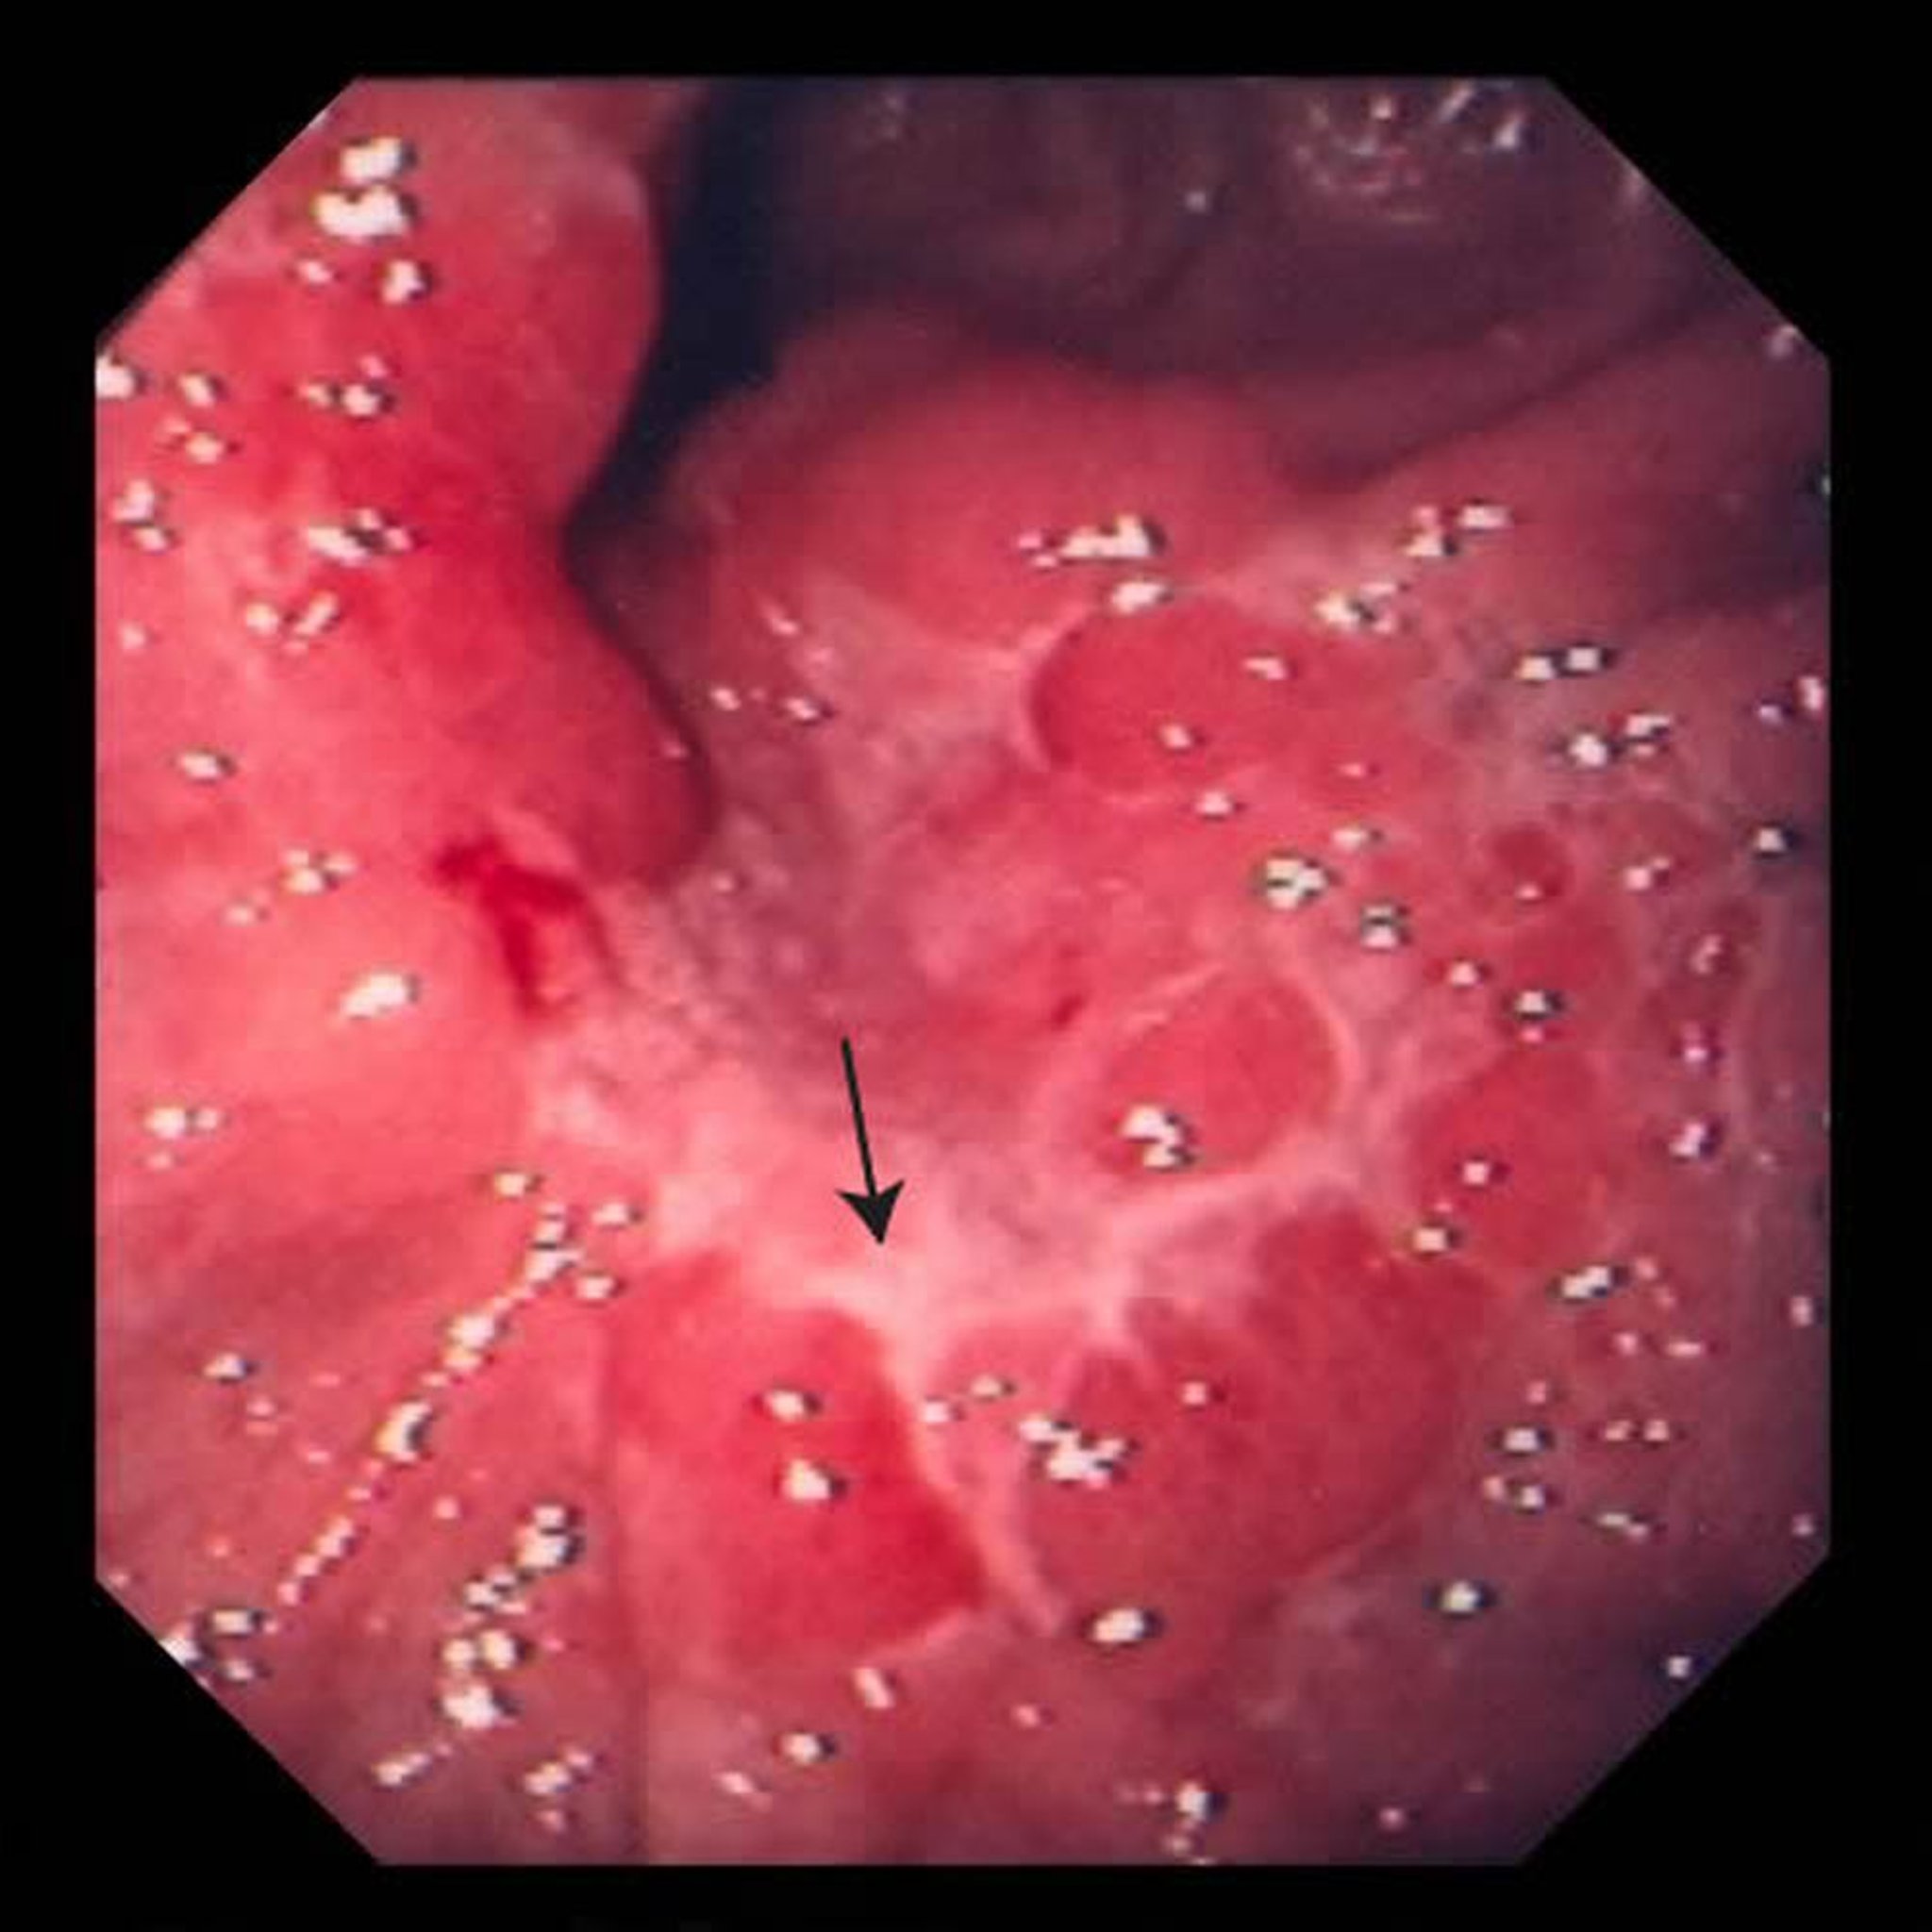

Auf diesem Bild ist ein Geschwür im Magen (Pfeil) zu sehen. Nach einer Biopsie stellten die Ärzte fest, dass es sich hierbei um ein Adenokarzinom handelte.

Bild von David M. Martin, MD.